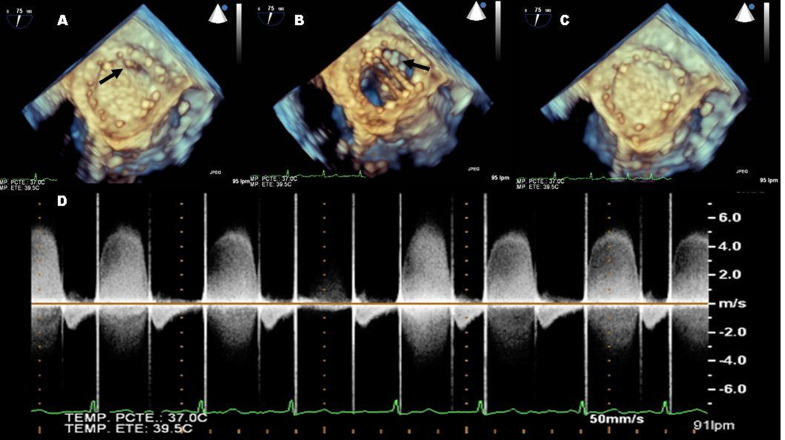

Case presentation: We present the case of a 72-year-old woman with a history of rheumatic heart disease and a mechanical mitral valve prosthesis. Although the initial postoperative course was uneventful, she developed rapidly progressive heart failure symptoms two years after surgery, secondary to newly onset severe mitral regurgitation. Transesophageal echocardiography was crucial in elucidating the underlying mechanism, revealing a ventricular mass intermittently interfering with the proper closure of the mechanical prosthesis. The main differential diagnoses regarding the origin of the mass included: remnants of the subvalvular apparatus, vegetation, thrombotic material and pannus formation. Given the clinical deterioration, surgical intervention was considered necessary despite the lack of precise knowledge regarding the nature of mass. Surgical exploration confirmed the rupture of the subvalvular apparatus involving the anterolateral papillary muscle as the underlying cause of the prosthetic dysfunction. Excision of the ruptured chordae tendineae and residual papillary muscle was performed with a favorable outcome and no complications.

Conclusions: This case illustrates a rare cause of late prosthetic mitral valve dysfunction: the entrapment of the subvalvular apparatus due to spontaneous rupture of the papillary muscle. Transesophageal echocardiography proved highly valuable in understanding the mechanism of dysfunction; however, surgical exploration ultimately established the definitive diagnosis and facilitated the correction of the issue.